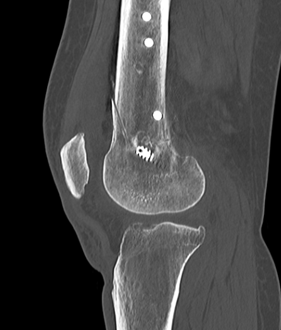

Avoiding medial cortical hinge fracture

Winkler et al KSSTA 2021

- 100 patients with mean age 31 undergoing OW DFVO

- 46% incidence of medial cortical hinge fracture

- reduced risk if osteotomy at or distal to adductor tubercle (27%)

- increased risk if osteotomy closer to medial cortex

- increased risk with increased height of osteotomy gap